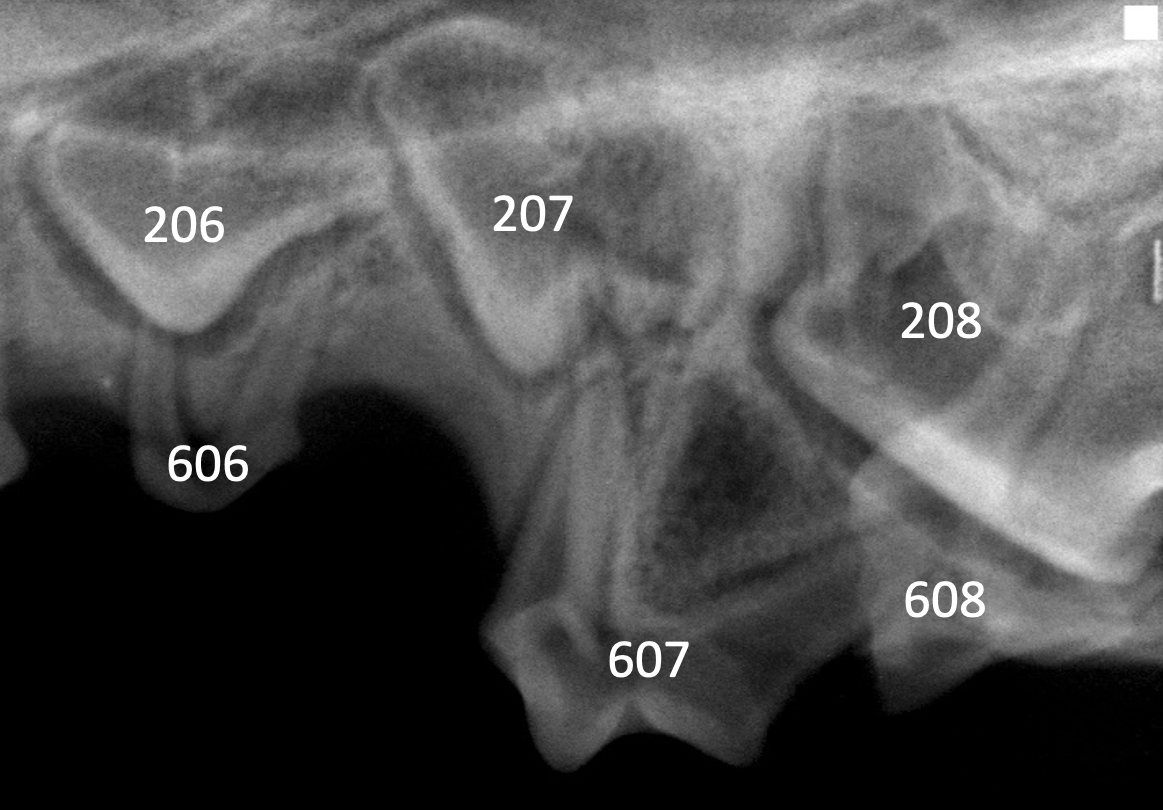

Dental radiography via a veterinary digital intraoral sensor and oral examination were performed with Uma under anesthesia. A slab fracture was seen on the palatal surface of 507 with pulpal exposure (Figure 2); a probe was easily inserted into the pulp cavity. No abnormalities were noted on the left side (Figure 3). Radiographs of the fractured tooth and its contralateral counterpart revealed a radiolucent area at the apexes of the mesial (ie, rostral, side of the tooth directed toward the first incisor) roots of 507.

There are no deciduous first premolar teeth. The anatomy of each deciduous premolar tooth is similar to the permanent tooth that erupts distal to it. Deciduous maxillary third premolar teeth (ie, 507/607) are thus anatomically similar to adult maxillary fourth premolar teeth and have 3 roots.5 Juvenile dogs with deciduous teeth often have some erupting adult teeth (ie, mixed dentition).

The treatment of choice for fractured deciduous teeth with pulpal exposure is extraction, which can prevent periapical infection that can damage underlying permanent tooth buds.3,4 Surgical extraction of a deciduous maxillary third premolar tooth is similar to extraction of an adult maxillary fourth premolar tooth; however, caution is needed because deciduous teeth are close to developing permanent tooth buds, and damage to buds can cause enamel hypoplasia or crown malformation in successor teeth.6 In addition, deciduous teeth have thin enamel walls and can break easily during extraction.7 Mixed dentition and unerupted developing adult dentition visible on dental radiographs can cause confusion and complicate preparation for extraction.

Underlying developing adult teeth can complicate interpretation of dental radiographs.